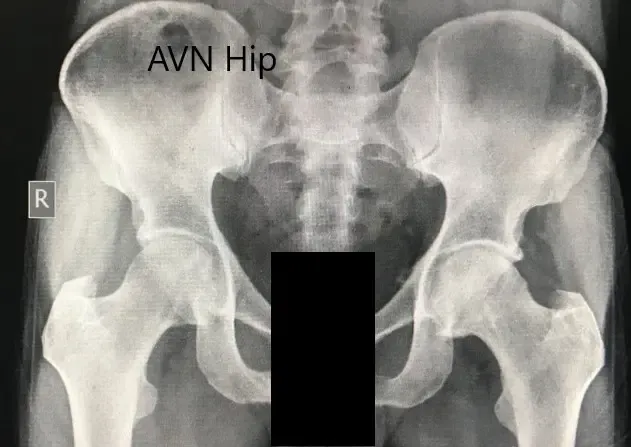

Se realizaron estudios de imagen en forma de radiografía que sugirieron esclerosis de la cabeza bilateral del fémur con cambios en acetábulo. Se realizó una resonancia magnética que sugirió necrosis avascular de ambas caderas.

Radiografía preoperatoria de la pelvis con ambas caderas en vista anteroposterior que muestra el AVN de las caderas bilaterales.